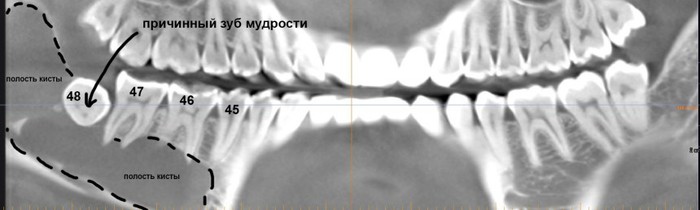

Но самое неприятное, что можно ждать от ретинированных зубов мудрости - это кисты.

Их источником является фолликул, окружающих зачаток зуба. Когда зуб прорезывается, фолликул исчезает, но в случае ретенции он сохраняется и может служить источником опухолей и кист. Иногда - достаточно больших и весьма опасных для здоровья.

И хотя всё это вполне себе лечится, согласитесь, что лучше не доводить себя до такого состояния.